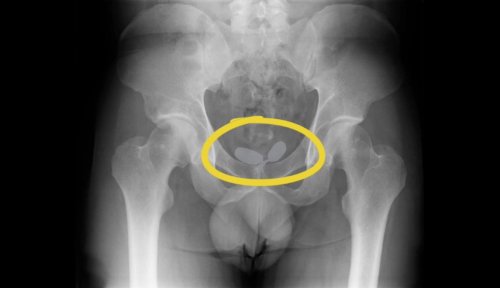

Alınan istihbarat doğrultusunda 2’si yabancı uyruklu toplamda 5 kişi yakalanarak gözaltına alınmıştı. Yapılan röntgen muayenesinde, uyuşturucu kaçakçılarının akıl almaz oyunu ortaya çıkarken, röntgen muayenesinde, Alman uyruklu kadının cinsel organında prezervatifler içerisine gizlenmiş uyuşturucular ele geçirildi. Diğer Alman yabancı uyruklu erkeğin ise uyuşturucuları anüsüne gizlediği belirlendi. Yapılan muayene sonrası; 21,19 gram eroin, 12,70 gram kokain, 7,76 gram amfetamin, 7 adet sentetik ecza ele geçirilirken, operasyon anları ise kameralara yansımıştı.